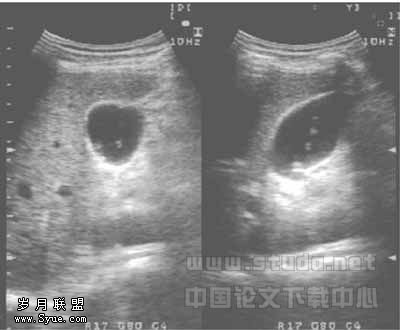

60例胆囊内可见点絮状物回声飘浮或沉积,见图3,改变体位后其形态变化明显,后无声影及慧星尾征,57例同时伴有上述肝内胆管的超声表现。

图3 华支睾吸虫病,胆囊内可见点絮状飘浮物回声